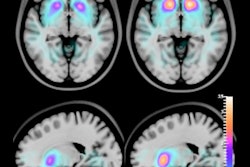

To evaluate the imaging performance of their proposed SPECT-CZT system, they used digital phantoms and realistic digital brain phantoms for conventional SPECT systems with comparable pixel sizes and radii of rotation. The proposed scanner offered image acquisition results up to approximately three times faster in acquisition time over conventional scan time at the same acquisition time per step.

The 3D activity map (left) and the 3D reconstructed images for the brain perfusion study using the three configurations of the conventional scanner and a proposed SPECT eight-ring CZT scanner in AS-3 and AS-5 acquisition modes with 100 iterations and post-processed using a 3D Gaussian filter with a sigma of 1 pixel. Image courtesy of Youngho Seo, PhD.The spatial resolution improvement, or deterioration, of the proposed scanner compared with the conventional scanner was dependent upon the location of the point source, the researchers noted. However, the overall performance improvements over the conventional scanner were measured by an increase in volume sensitivity of up to 1.7 times.